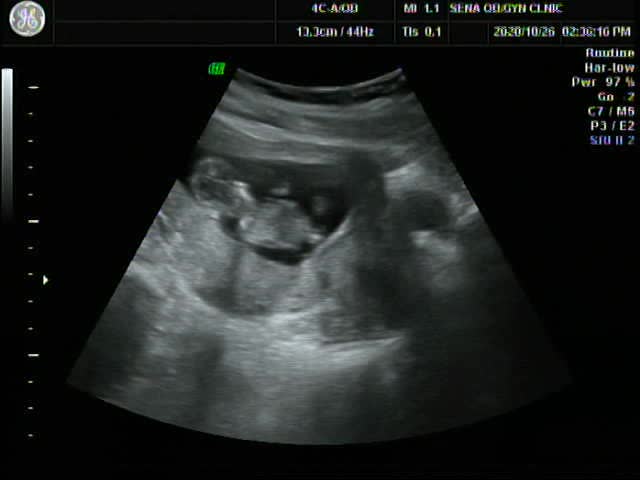

15주~16주(2차 기형아검사)

16주 2차 기형아 검사를 가기전..15주차에 세나를 다시 방문했어요!ㅎㅎ우리 찰떡이 얼마나 컸나 궁금한 마...